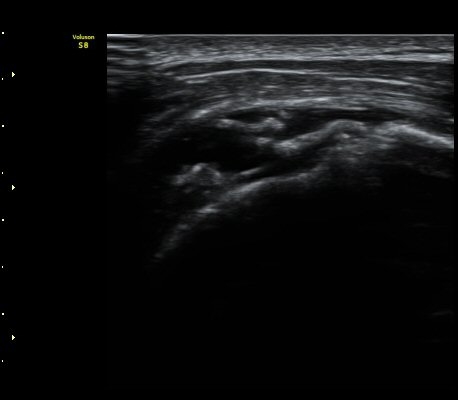

À̵ιڱ٠Ⱦ´Ü¸é°Ë»ç¿¡¼­ °üÀý³» ¼ö¾×Àú·ù´Â °üÂûµÇÁö ¾Ê´Â´Ù(»çÁø 1)